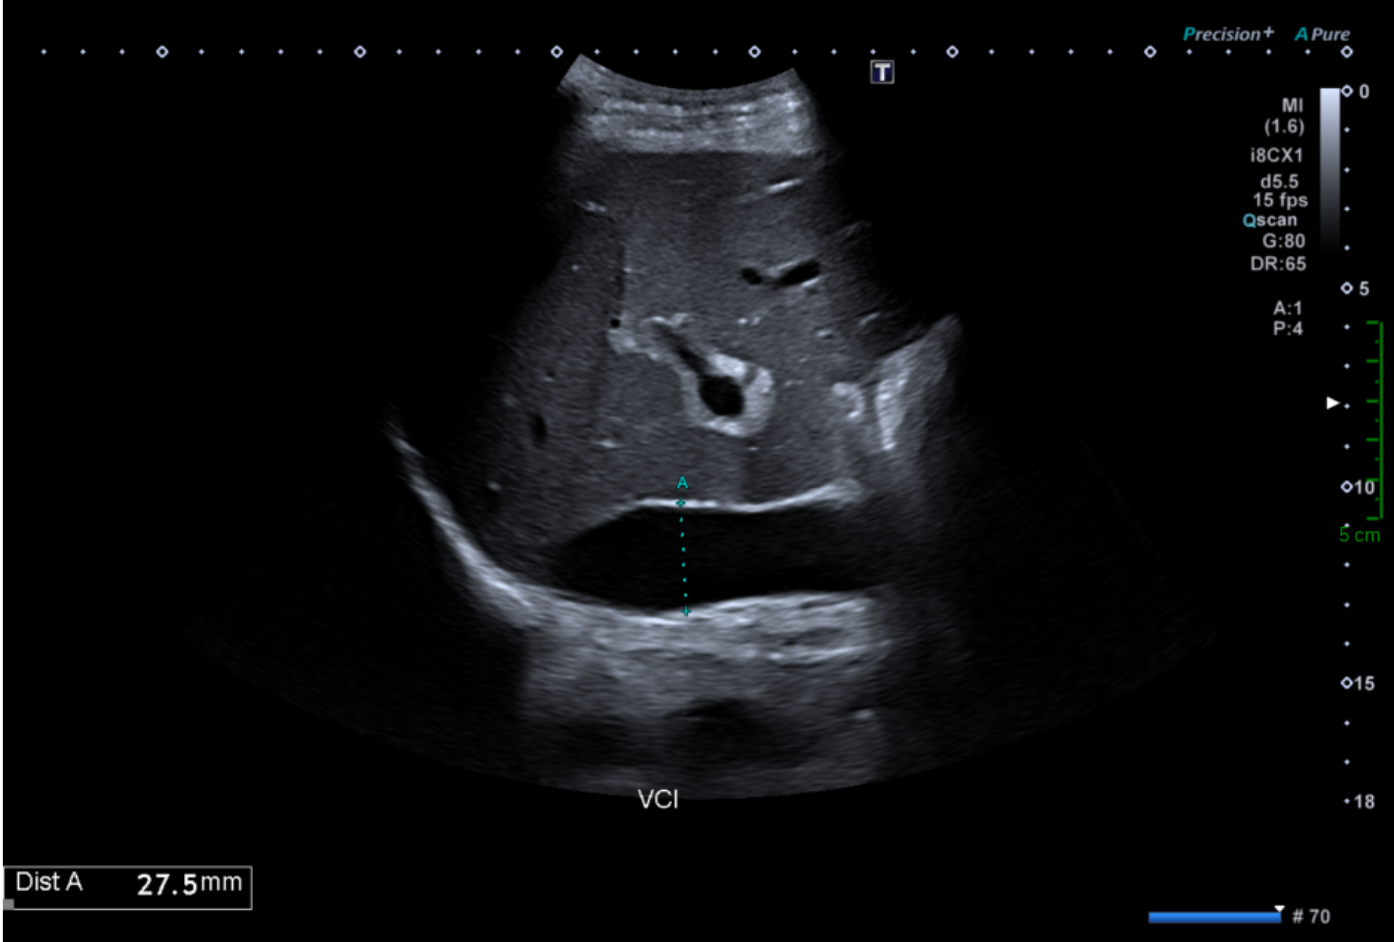

Une dilatation de la veine cave inférieure.

Le calibre normal de la veine cave inférieure varie au cours du cycle respiratoire : il est maximum en inspiration bloquée (manœuvre de Valsalva) et minimum, voire collabé, en fin d'expiration. Cette cinétique est un critère important de normalité hémodynamique. Le diamètre en expiration profonde ne doit pas dépasser 25 mm

VCI dilatée non compliante